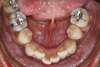

Prognathisme traitée en technique lingual

A-début